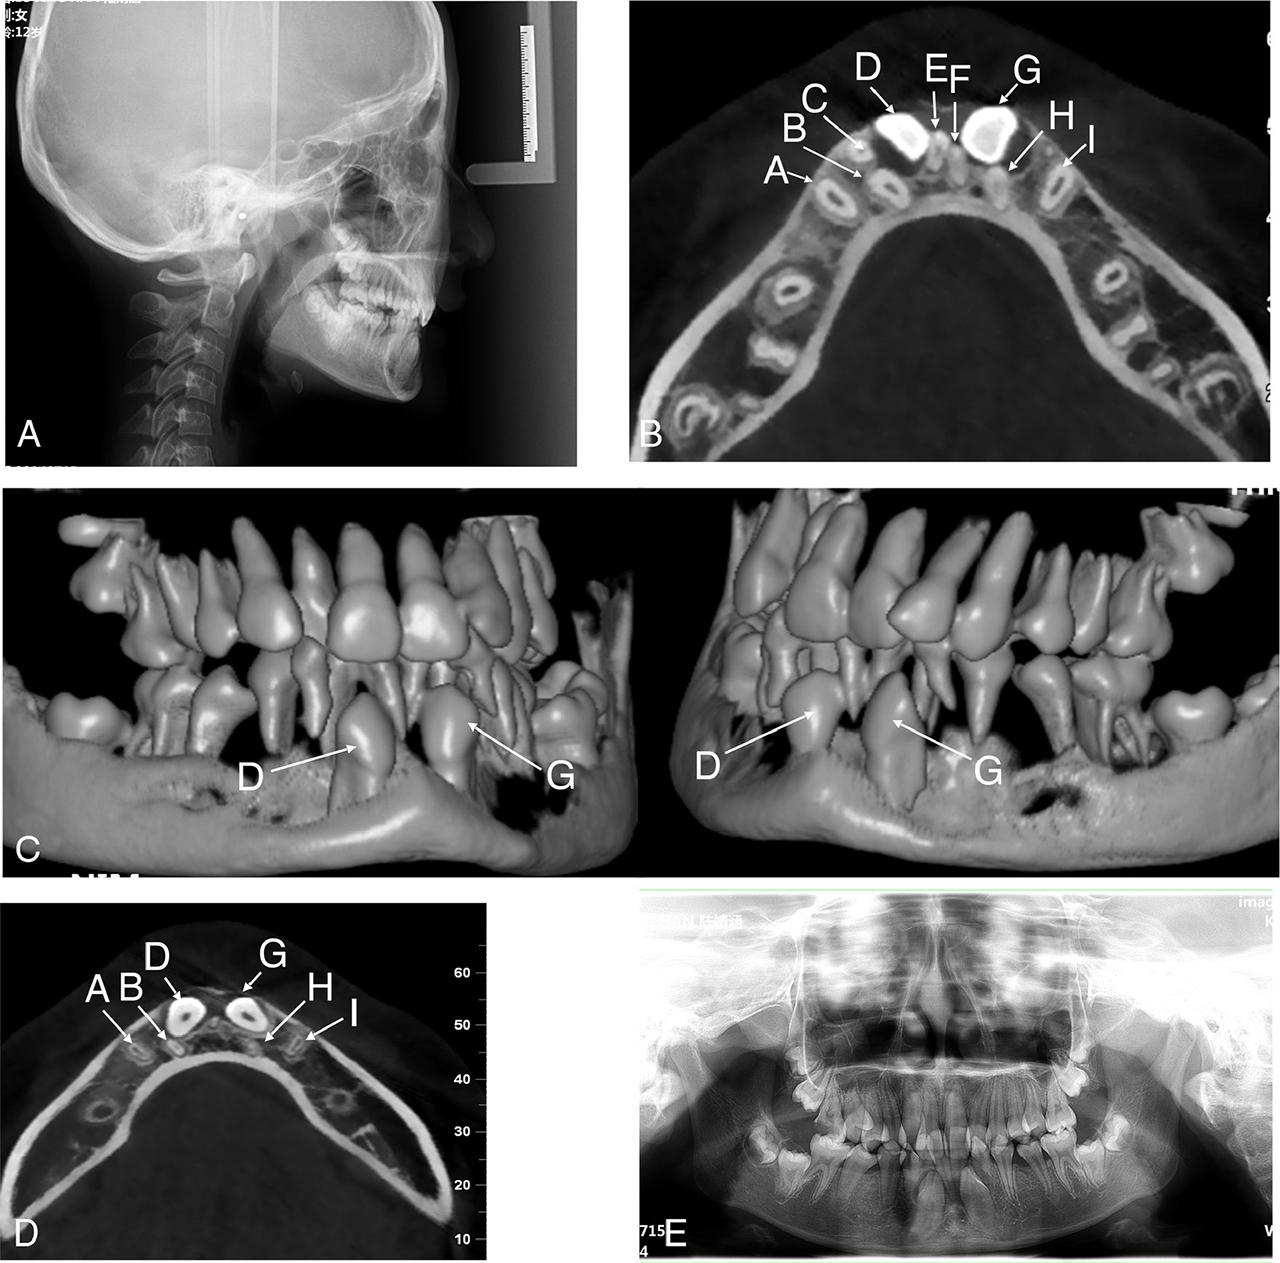

Figure 2